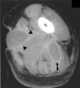

Hyperechoic renal mass